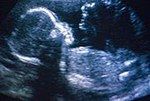

La ecografía es un examen médico que permite obtener una imagen de vídeo de los órganos examinados. El examen se efectúa gracias a un aparato, el ecógrafo.

El radiólogo pasa una sonda por la superficie de la piel, sobre el órgano a examinar. Los ultrasonidos emitidos por la sonda se reenvían y analizan informáticamente y, a continuación, se traducen en imágenes de vídeo.

En lo relativo a la observación médica del embarazo, la ecografía permite seguir “en directo” el desarrollo del bebé, medir su crecimiento.